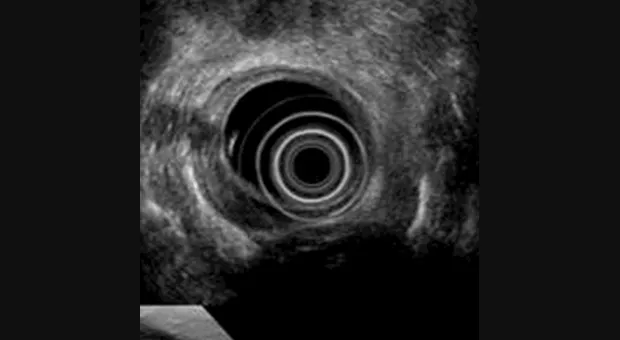

Правильное установление стадии развития опухоли необходимо для выбора приемлемого метода лечения. С развитием эндоскопического УЗИ увеличилась его точность определения глубины инвазии опухоли (Т). Kelly с соавторами [2] объединил результаты 27 статей посвященных эндоскопическому УЗИ в определении стадии рака пищевода и желудка по TNM и пришел к выводу, что эндоскопическое УЗИ имеет высокую степень точности в установлении стадии заболевания.

Caletti с коллегами [3] сообщают, что точность эндоскопического УЗИ в установлении стадии достигает 80 % по Т и около 77 % по N. В последнем опубликованном обзоре [4] точность установления стадии рака желудка варьировало от 67 % до 92 %. Согласно данных представленных Murata с коллегами [5] чувствительность и специфичность определения инвазии с мышечную пластинку слизистой оболочки при использовании зонда с частотой 20-MHz была 97 % и 87 % соответственно. В дополнение к этому, по данным крупнейшего Американского исследования по резекции слизистой [6], наблюдается высокий уровень совпадения между данными полученными при высокочастотном ультразвуковом сканировании и морфологическими находками (96 %).